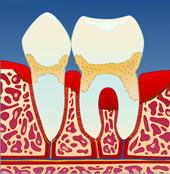

figur I figur II figur III figur IV

Dersom belegget ikke fjernes, vil det over tid forkalkes og bli hardt. Det er dette vi kaller tannstein. Tannstein forsterker betennelsen som fører til at benet rundt tennene brytes ned (II). På denne måten vil tannstein og bakteriebelegg kunne strekke seg stadig lenger ned langs rotoverflaten (III). Bentapet kan over tid bli så omfattende at tenner løsner og eventuelt må fjernes (IV).